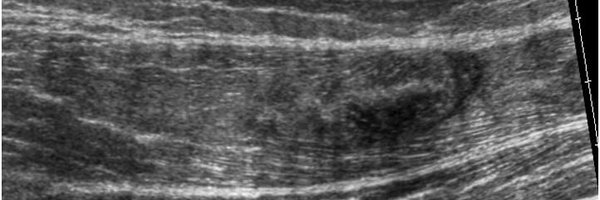

Trabajando en mis charlas para el Curso de Ecografía ARS 2024. Como muestra, aquí os dejo una imagen del ligamento peroneoastragalino anterior en una visión anterior Nos vemos en el curso ARS!